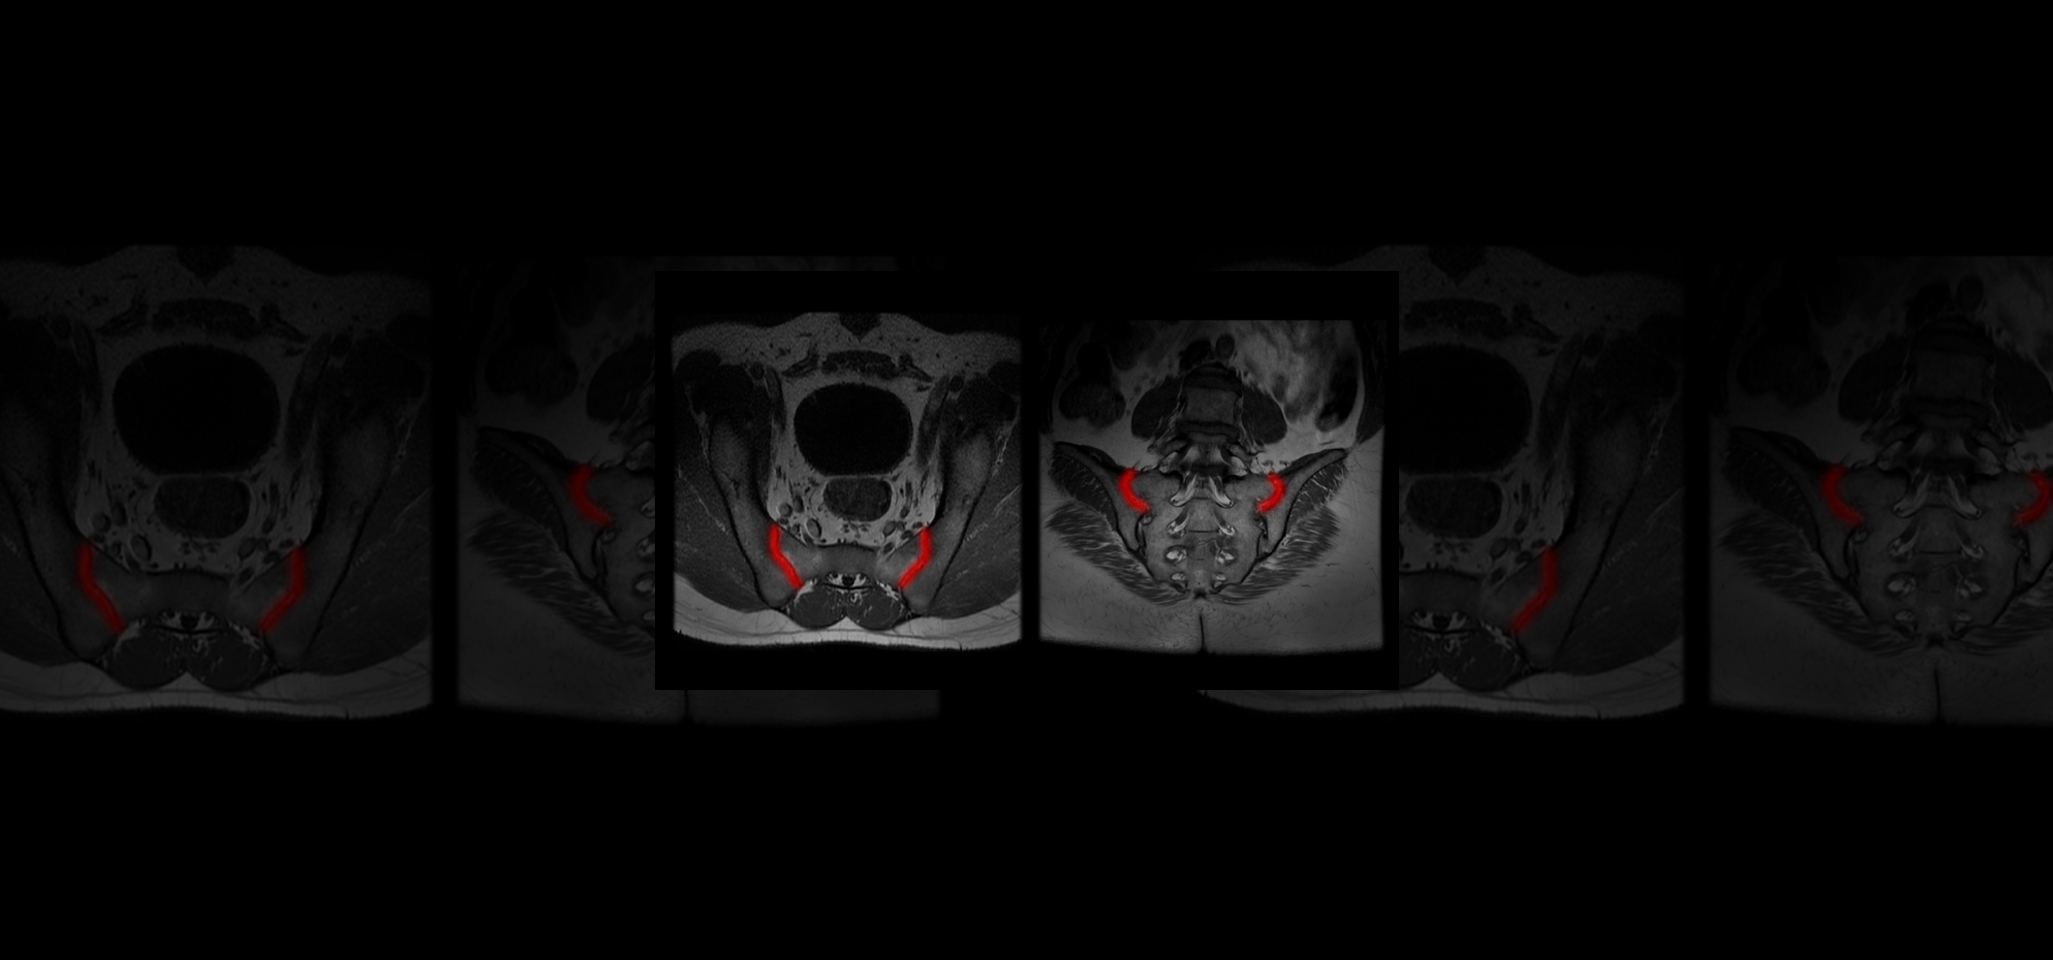

Quibim, in collaboration with a top-tier biopharmaceutical company, is conducting a retrospective observational real-word study with data from six sites world-wide (NCT06591481). The training dataset consists of 600 MRIs of the sacroiliac joint (SIJ) including a T1-weighted and STIR and/or T2 fat saturated sequence in coronal-oblique planes acquired at diagnosis and follow-up. For the validation process, an external sample of 200-300 MRIs with and without axSpA are being collected. QP-Insights® platform is being used for the image collection and processing. A double reading according to the Assessment of Spondylarthritis international Society (ASAS) criteria is being performed by radiologists with 12+ years of experience and a third reader for adjudication. The reading process consists of the classification into axSpA +/- and identification of the main findings: bone marrow edema (BME), ankylosis, erosion and fat metaplasia. An artificial intelligence (AI) based classification model will be developed to categorize patients as axSpA-positive (axSpA+) or axSpA-negative (axSpA-). Additionally, as an exploratory objective, the model will further stratify patients based on the main findings identified.